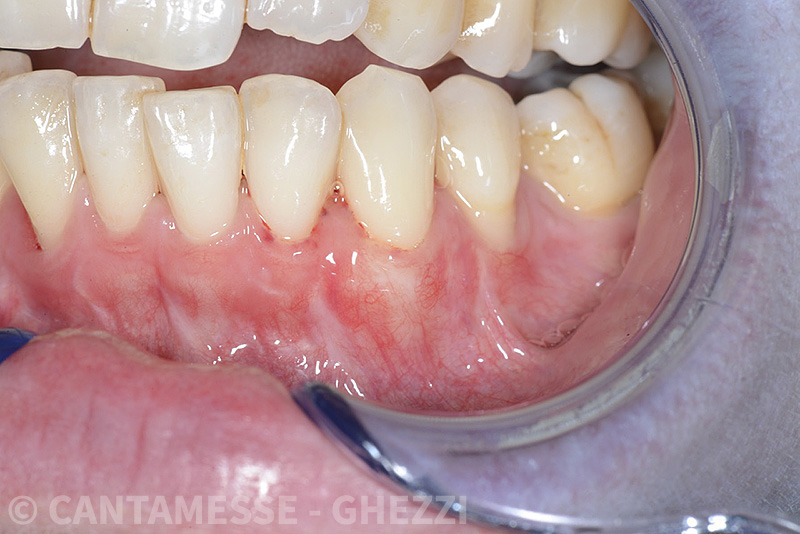

PREMESSA: in seguito all’estrazione dell’incisivo laterale superiore di destra, resasi necessaria per cause batteriche, si decide di affrontare il caso con il posizionamento di un impianto in sostituzione dell’elemento mancante dopo guarigione del sito infetto. Con tecniche rigenerative sia dei tessuti ossei mancanti a causa dell’infezione pregressa, sia dei tessuti gengivali che appaiono inizialmente troppo spostati in alto, si ripristina una corretta morfologia delle parabole (contorni) gengivali e delle papille interdentali (triangoli di gengiva tra due denti vicini).

Vengono utilizzati 2 tipi di provvisori: il primo, cementato ai denti vicini, viene utilizzato dal momento dell’estrazione del dente fino ad impianto osteointegrato (circa 6 mesi); il secondo, avvitato direttamente all’impianto, ha una funzione di prova estetica ma soprattutto di guida per la maturazione dei tessuti gengivali peri-implantari portandoli verso la maturazione completa prima di posizionare la corona finale in disilicato di litio.